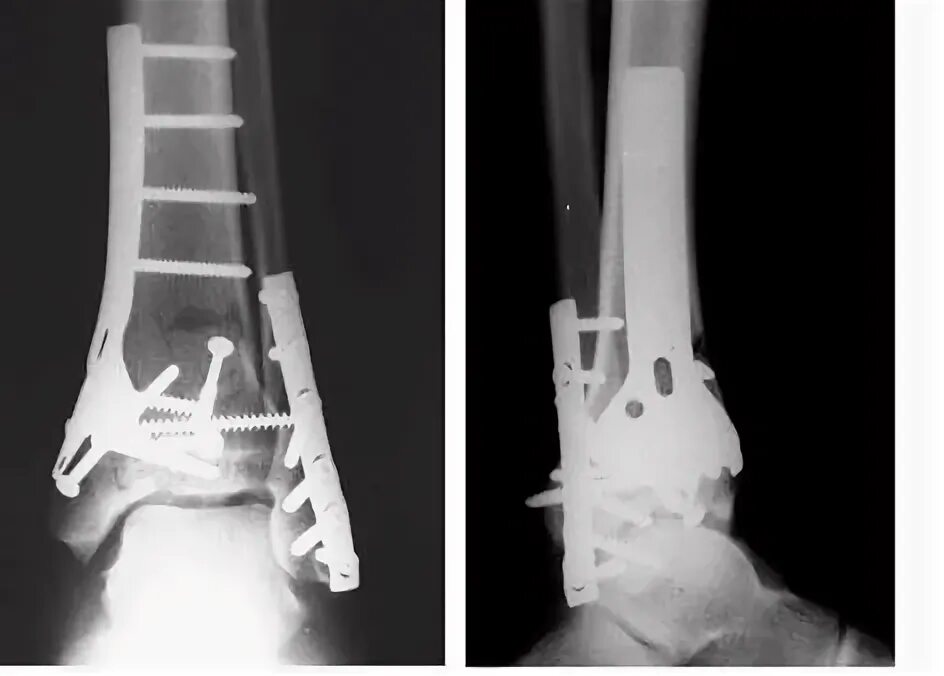

Лодыжка перелом смещение операция пластина